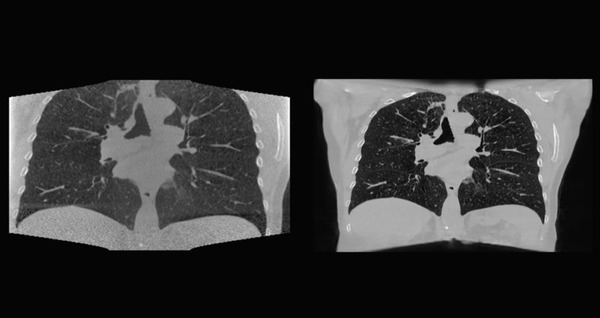

世界トップクラスのがん研究および治療センターであるオランダがん研究所(以下、NKI)は、NVIDIA AI Enterpriseのソフトウェアスイートを使用して、現在一般的に使用されているものより高精度の3DがんスキャンでAIワークロードをテストしている。NKIのAIモデルは以前、低解像度の画像でトレーニングしていた。しかし、NVIDIA AI Enterpriseが提供する大容量のメモリを利用することで、NKIの研究者たちは高解像度の画像でトレーニングを行うことが可能になった。このような解像度の向上により、臨床医は患者が治療を受けるたびに、腫瘍のサイズや位置をより正確に特定できるようになる。

NKIの研究者はHewlett Packard EnterpriseのコンポーザブルソフトウェアシステムであるHPE Synergy上で動作するNVIDIA AI Enterpriseを使用し、2Dおよび3Dの大規模なデータソースとAIを組み合わせて、放射線治療の各セッションの前に腫瘍の位置を特定できるディープラーニングモデルを構築した。

「医師は治療当日にCTスキャンの代わりにこのソリューションを使用して、治療計画を最適化し、放射線治療計画を検証することができます。」と、オランダがん研究所のグループリーダーであるジョナス トゥーエン (Jonas Teuwen)氏は述べた。

また、トゥーエン氏のチームはNVIDIA AI Enterpriseを使用して、シリコンバレーでホストされているサーバー内のNVIDIA A100 80GB GPUでワークロードを実行した。同チームの畳み込みニューラルネットワークは3か月かからずに構築され、300枚もない臨床肺CTスキャンでトレーニングされ、その後、再構築されて頭頸部のデータに一般化された。